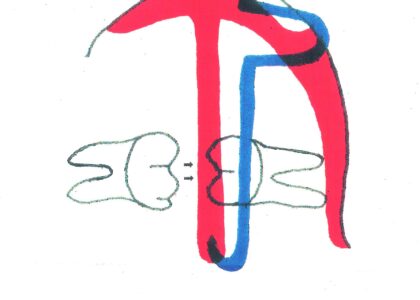

- セファロ